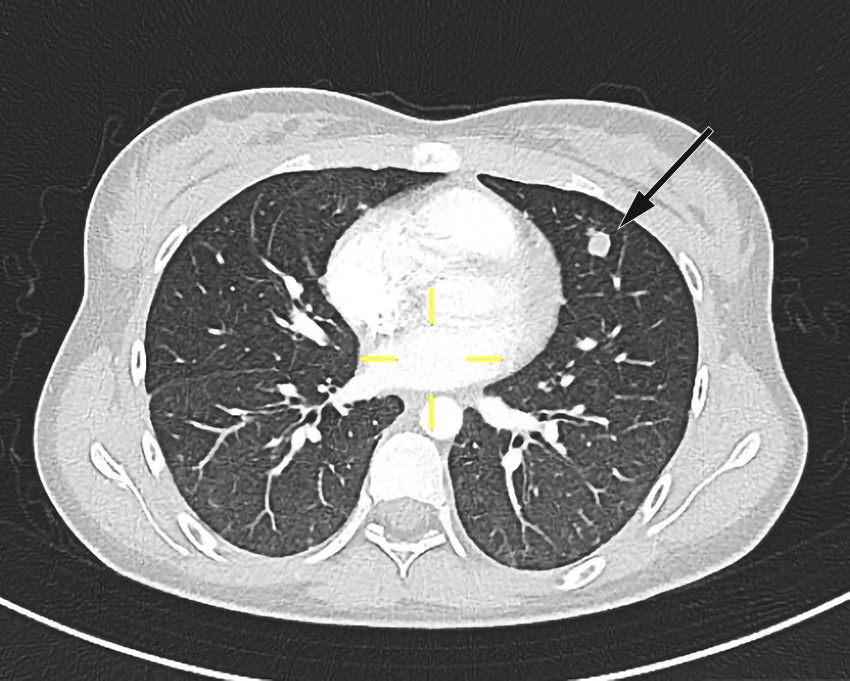

Pasienten ble videre undersøkt av vakthavende øre-nese-hals-lege. Man mistenkte abscedering, men trismus og smerter gjorde at det var vanskelig å få gjennomført en fullgod halsundersøkelse. Det ble derfor rekvirert CT collum. CT-funnene var forenlig med tonsillær/peritonsillær abscess bilateralt samt høyresidig trombosert vena jugularis med ledsagende tromboflebitt og flegmonøs betennelse (figur 1). På bakgrunn av dette ble Lemierres syndrom mistenkt. Abscessene ble vurdert som ikke modne for drenering, og det ble anbefalt bytte av antibiotika til klindamycin intravenøst, 600 mg × 3, hvilket ble startet opp neste dag. Grunnet trombosetendensen ble det også forordnet lavmolekylært heparin (enoksaparin), dosering 60 mg subkutant morgen og 40 mg subkutant kveld. P-piller (etinyløstradiol) ble seponert, da disse kan gi økt trombosetendens.

Pasienten fikk smerter i venstre del av toraks på dag 2. CT toraks og abdomen viste funn forenlig med septiske embolier i begge lunger og mulig infarktkomponent i høyre underlapp (figur 2, figur 3). I tillegg var det lett forstørret lever og milt, periportalt ødem samt små mengder fri væske i bekkenet (mulig fysiologisk). Det var også beskrevet mistanke om tromber i vena subclavia og vena axillaris på høyre side. Dag 3 så man oppvekst av penicillinfølsomme Streptococcus anginosus i blodkultur. Serologiske prøver viste svakt positivt Epstein-Barr-virus (EBV)-viralt kapsidantigen (VCA)-IgG, svakt positivt EBV-VCA-IgM og negativt EBV-EBNA-IgG. Intravenøst benzylpenicillin og klindamycin samt antikoagulasjonsbehandling med lavmolekylært heparin (enoksaparin) ble kontinuert.